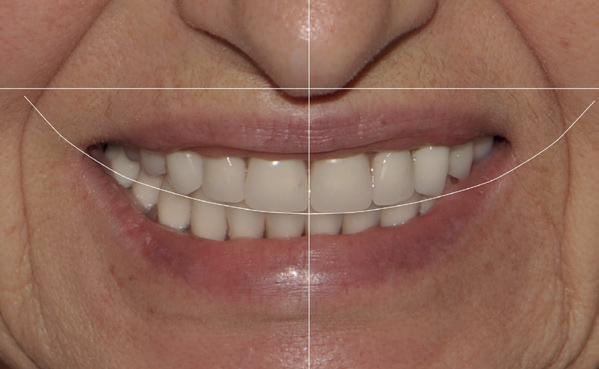

In de prothetische fase (zie foto’s) is in de bovenkaak gebruikgemaakt van verschroefde zirconia bruggen, die enkel buccaal zijn opgebakken. Deze bruggen zijn verlijmd op individuele, geanguleerde titanium abutments. In de onderkaak is een verschroefde kunststofbrug op een titaniumbasis (wrap-around) gemaakt. Voor deze combinatie is gekozen vanwege een minder hinderlijk tikkend geluid bij functie en kleinere kans op breuk van de keramiek. Een nadeel is verhoogde slijtage van de kunststof elementen, maar deze zijn in de jaren later eenvoudig te vervangen op de bestaande brug. Ondanks alle digitale mogelijkheden is de afdruk en registratiefase analoog uitgevoerd, omdat in ervaring van de behandelaren dit bij deze totale rehabilitaties op implantaten nog altijd de grootste precisie oplevert. Er is afgedrukt met impregum in individuele lepels en de pasvorm is gecontroleerd met rigide duralay bars. De relatie wordt vastgelegd zoals bij een volledige prothese met waswallen en pijlpuntregistratie. De opstelling in was wordt gepast en laatste correcties worden gemaakt in samenspraak met de patiënt, de restauratieve tandarts en de tandtechnicus. Na het vastzetten van de suprastructuren worden de schroefgaten afgesloten met composiet.

in de zes maanden bij de mondhygiënist voor peri-implant reiniging, pocketmetingen, mondhygiëne instructies en controles. De AirFlow wordt daarbij standaard gebruikt. Verder wordt de patiënt na één, drie en zes jaar gezien voor controle van de suprastructuren door de restauratieve tandarts. Uit de röntgenfoto’s kan afgeleid worden dat het botniveau gelijk blijft over tijd. Klinisch ziet de situatie er infectievrij uit; de patiënt onderhoudt het zelf netjes met ragertjes, een elektrische tandenborstel als ook de Waterpik.

uitgevoerd met restauratief tandarts Paul de Kok, KVPA). 12. Eindresultaat.